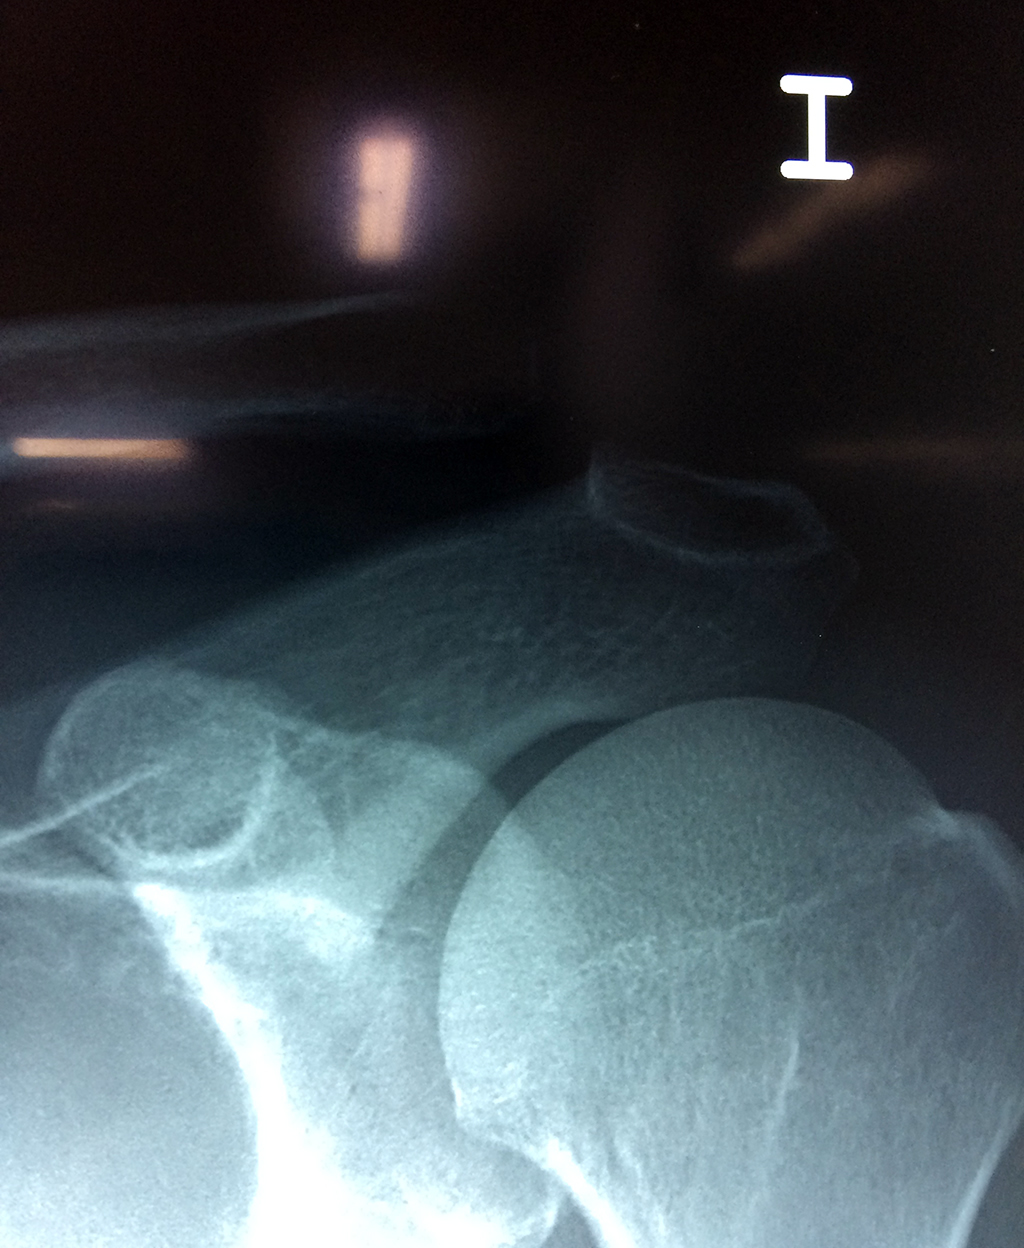

Clavícula

La clavícula es un hueso largo, con forma de "S" itálica, situado en la parte anterosuperior del tórax. Junto con la escápula forman la cintura escapular. Se puede palpar por toda su longitud y se extiende del esternón al acromion de la escápula, siguiendo una dirección oblicua lateral y posterior.